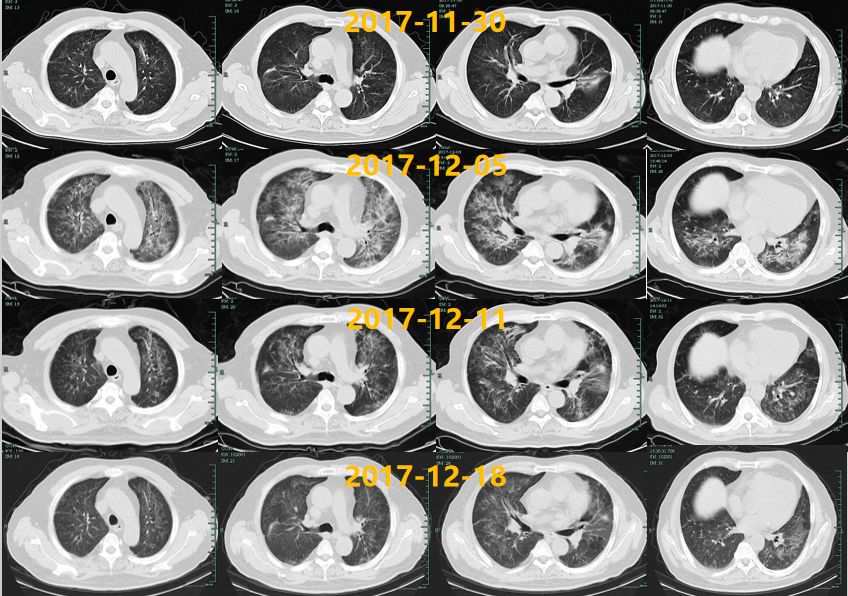

临床转归:12.6开始抗病毒治疗后患者胸闷气急情况逐渐缓解,肺部影像学吸收好转,患者12.18出院。

【图3】诊治期间肺部CT变化